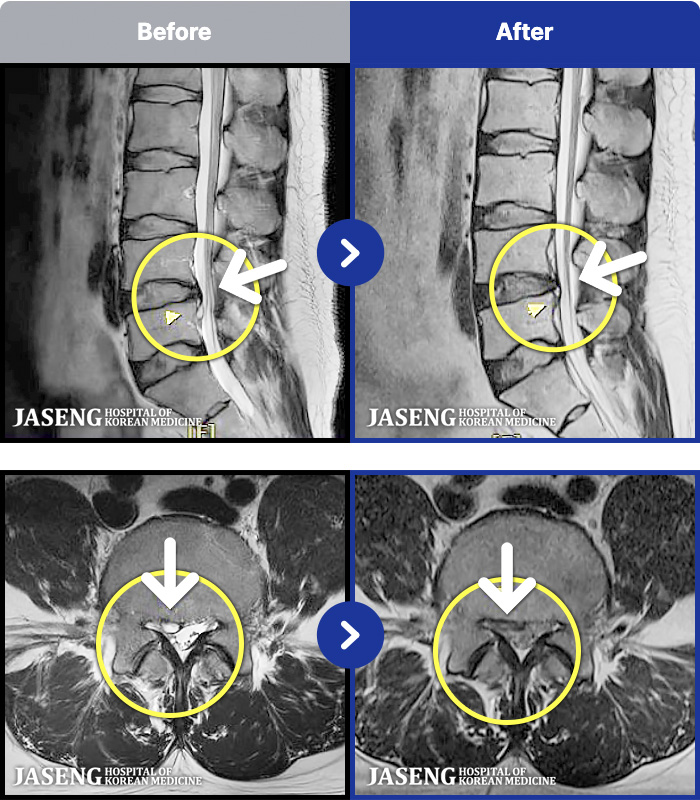

97 MRI ũ ʸ Ȯϼ.

ȯںп Ǹ ǿ ԿǾ, ο ġ ۿ Ƿ ġḦ Ͻñ ٶϴ.